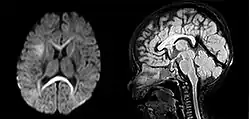

Tanto a angiografia por tomografia computadorizada (ATC) como a angiografia por ressonância magnética (ARM) demonstraram ser efetivas no diagnóstico de malformações vasculares intracranianas após a hemorragia intracerebral.[13] Com tanta frequência, um angiograma de tomografia computadorizada será realizado para excluir uma causa secundária de hemorragia[14] ou para detectar um "sinal local".

A hemorragia intraparenquimatosa pode ser reconhecida na tomografia computadorizada porque o sangue aparece mais brilhante do que outro tecido e é separado da mesa interna do crânio por tecido cerebral. O tecido que envolve um sangramento é muitas vezes menos denso do que o resto do cérebro por causa do edema e, portanto, aparece mais escuro na tomografia computadorizada.[14]